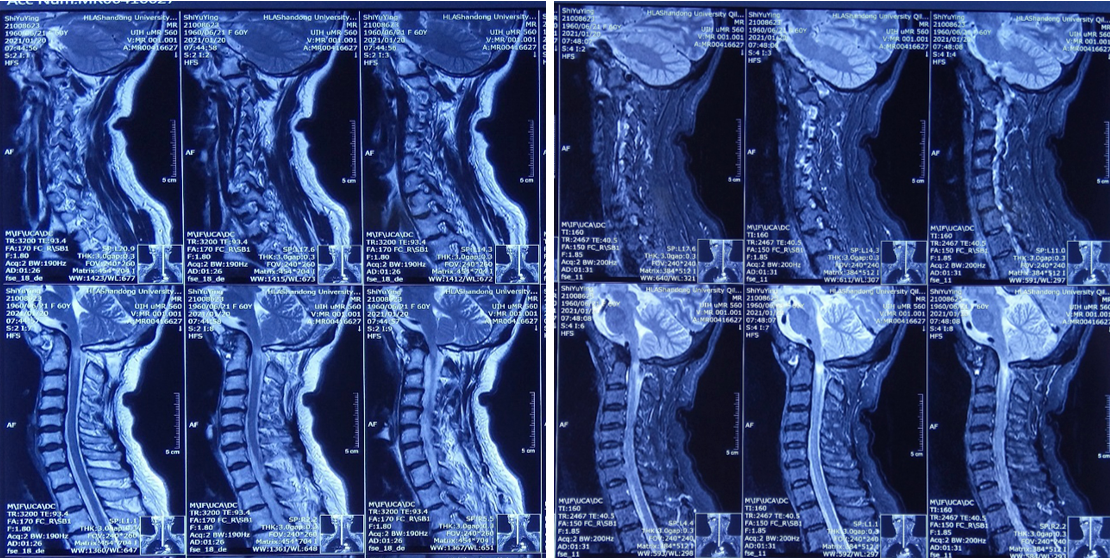

颈髓MRI:

颅底凹陷症、寰枕融合;寰枢关节脱位并延髓脊髓变性或损伤;颈椎退行性变;C2/3、C3/4、C4/5、C5/6、C6/7椎间盘突出并C4/5水平椎管狭窄。

患者术前部分影像学资料

影像学资料显示寰枢椎脱位,脊髓受压明显